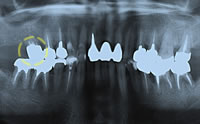

治療後

治療後のパノラマX線写真パノラマX線写真